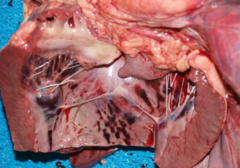

acute, severe, ecchymotic, Endocardial Hemorrhage

Front

morphological diagnosis